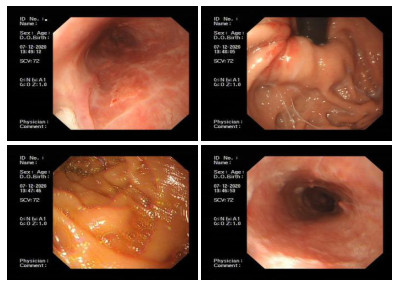

1 资料与方法患者,女性,67岁,因“上腹部不适近1个月,反复呕血2 d”来院。患者近1个月生活压力大,喜食辛辣及过热食物,进食后有上腹部不适感,休息0.5~1 h后缓解,未诊治。2 d前进食槟榔后即刻出现咽喉部至胸骨下端自上而下持续性、撕裂性疼痛感,5 min出现数十次喷射性呕血,鲜红色,每次呕血50 mL左右。就近医院就诊,随访血红蛋白由117 g/L下降至93 g/L。心脏标志物、凝血功能、肾功能电解质基本正常。胃镜示食管内见巨大青紫色曲张静脉,中下段为著,管腔狭窄,局部表面渗血;胃窦见一大小约2.0 cm×2.0 cm带蒂息肉。胸部增强CT示(图 1):(1)所见胸段食管壁弥漫性不均匀增强,下段食管为著,建议胃镜检查及病理活检;(2)双肺散在纤维灶,主动脉和冠状动脉硬化,双侧胸膜增厚,少量胸腔积液。胸主动脉CTA示:食管中下段占位。给予禁食、补液、止血及对症等治疗后,仍有胸骨后持续性疼痛,反复呕血未见明显好转,血红蛋白进行性下降,遂呼叫120转至本院。

| 胸段食管壁弥漫性不均匀增强,下段食管为著(白色箭头所指为管壁增厚的食管) 图 1 患者发病当天的外院胸部增强CT |